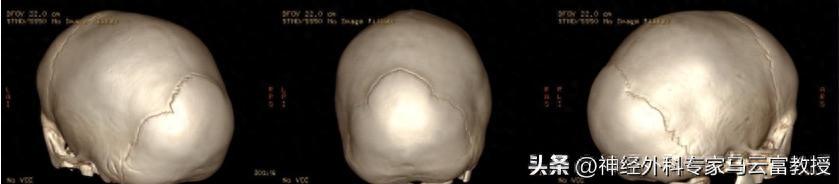

顱縫早閉的診斷標準從兩方面來看:一方面是臨牀上的表現即頭型的異常,但是這個頭型的異常需要由神經外科的醫生來判斷;第二個就是可以摸到明顯的一個鼓脊,那麼和這個頭型是相符合的,能夠摸到可能閉合的這條骨縫上的鼓脊,這一個是症狀。再一個非常重要的客觀的檢查就是3D的顱骨CT的三維重建,在這個三維重建上可清晰地看到哪些骨縫是正常的,哪些骨縫是提前閉合的,和臨牀表現能夠對的上,基本上就可以做出一個明確的診斷。

目前我科有3例顱縫早閉(矢狀縫早閉),待手術進行,讓我們爲患兒加油